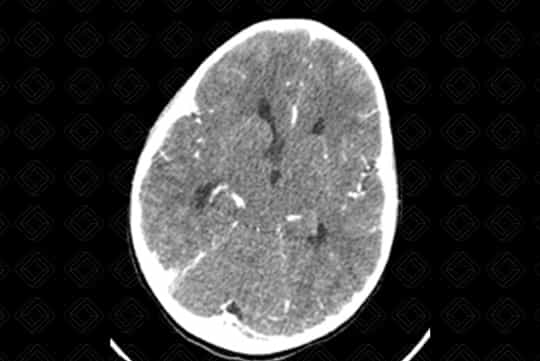

Texto alternativo para a imagem Figura 3. Créditos: Dra. Elazir Mota - Rio de Janeiro/RJ

Descrição das figuras 1, 2, 3, 4 e 5: Tomografia computadorizada do crânio após administração do contraste venoso nas reformatações axial e coronal. Paciente de 4 anos com lesão discretamente captante de contraste (asterisco - figura 2) no corno anterior do ventrículo lateral direito, causando obstrução do forame de Monro e hidrocefalia secundária, de etiologia obstrutiva. [cms-watermark]